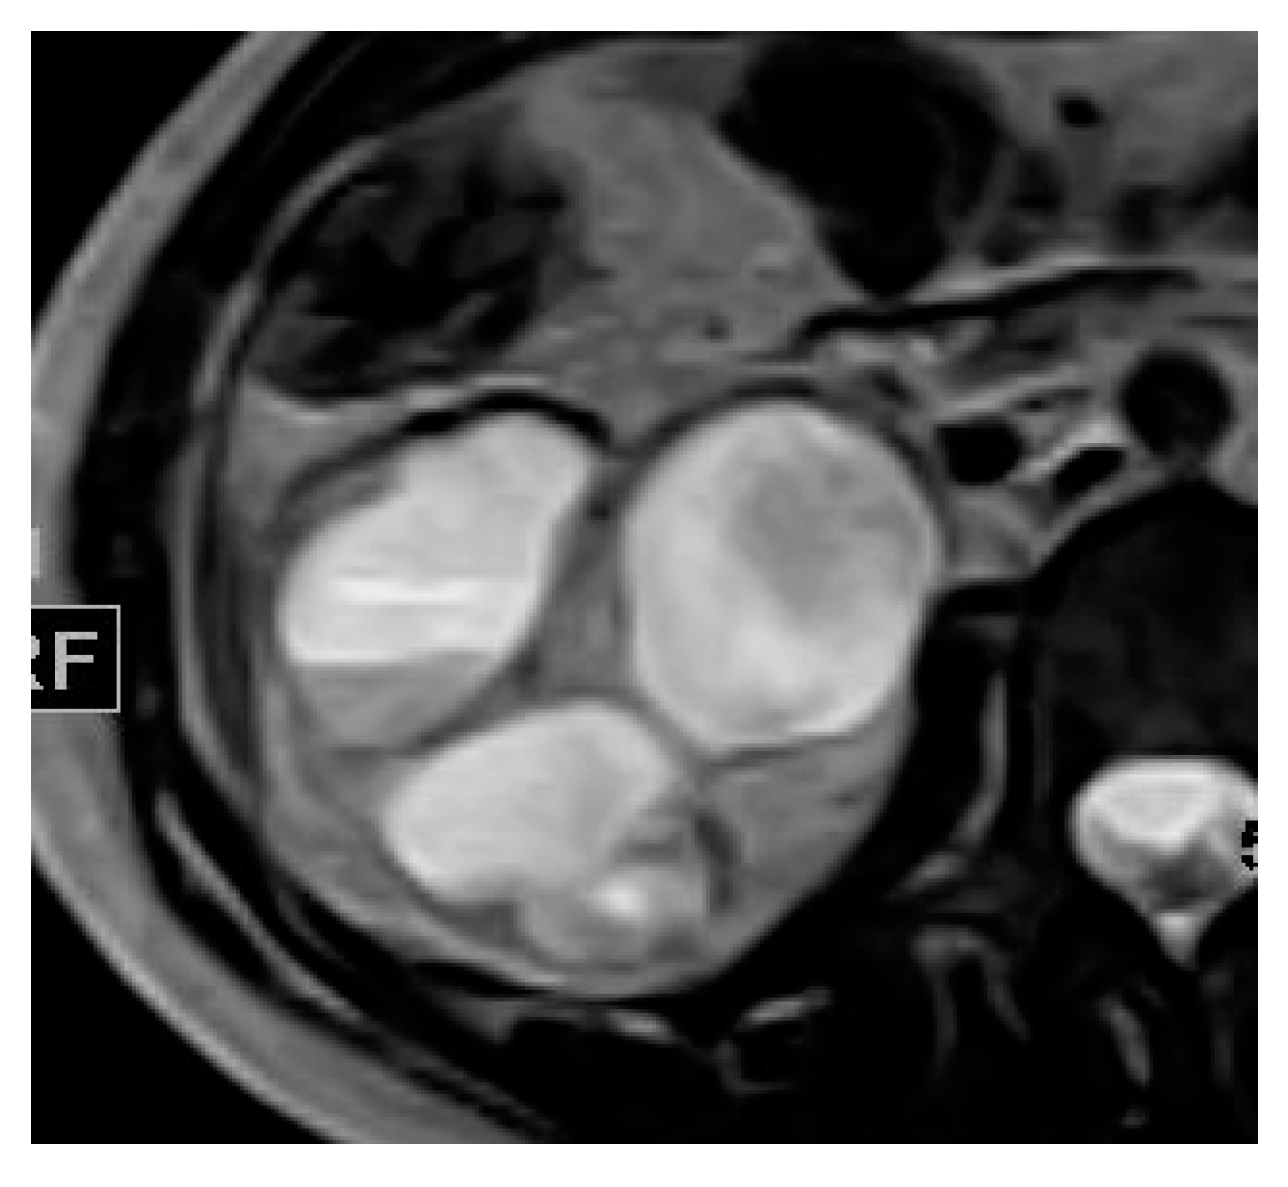

2.15. Acute Bacterial Prostatitis and Prostatic Abscess

| Prostatic abscess | Non enhancing fluid collection with peripheral or septal enhancement and non-enhancing central fluid. Possible extraprostatic extension |